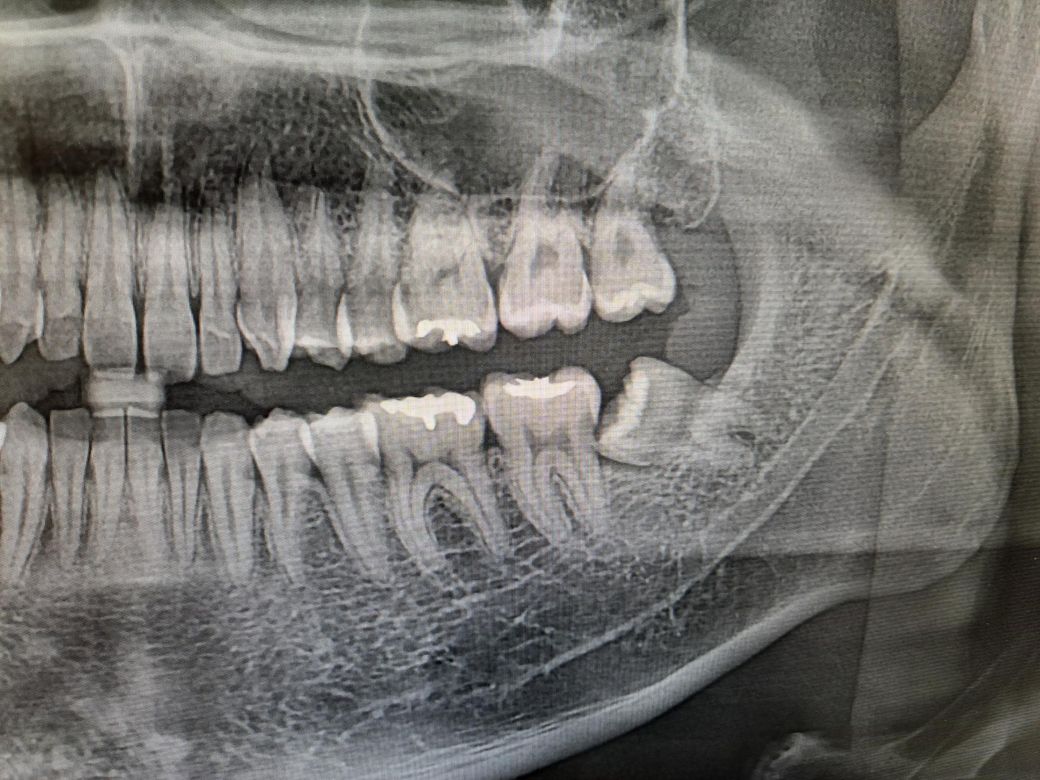

• 2번 째 사진

빼봐야 압니다 파노라마 사진보고 사랑니 옆 어금니가 썩었다고 단언하는 건 엉터리입니다 물론 확률상 충치가 있는 경우가 많지만 사랑니 빼고 다시 정밀한 치근단 사진(작은 엑스레이 사진) 찍어보면 충치 아니고 그냥 왜곡(엑스레이상 그림자의 일종)인 경우도 간혹 있습니다

저게 옆면 충치가 맞다면, 크라운을 씌워야 하므로 신경치료는 피하긴 어렵습니다

해당 사진만으로는 정확한 여부 알 수는 없으나 사진상 보이는 것 보다는 실제 더 깊을 가능성이 높습니다. 깊다면 단순 우식 제거뿐만 아니라 신경치료 병행할 가능성 옾으며 정확한 판단은 사랑니 발치 후 확인해봐야할 것으로 보입니다. 너무 미루지 마시고 지치 발치하시길 바랍니다.

하악 지치의 경우 신경관과 인접해 있으므로 관련합병증에 대한 충분한 이해 후 발치 진행하시길 바랍니다.